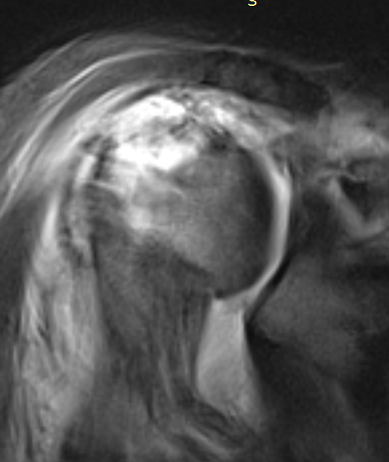

MRI

Rotator cuff tears

MRI with supraspinatus tear, Hill Sachs lesion and significant glenoid bony deficiency